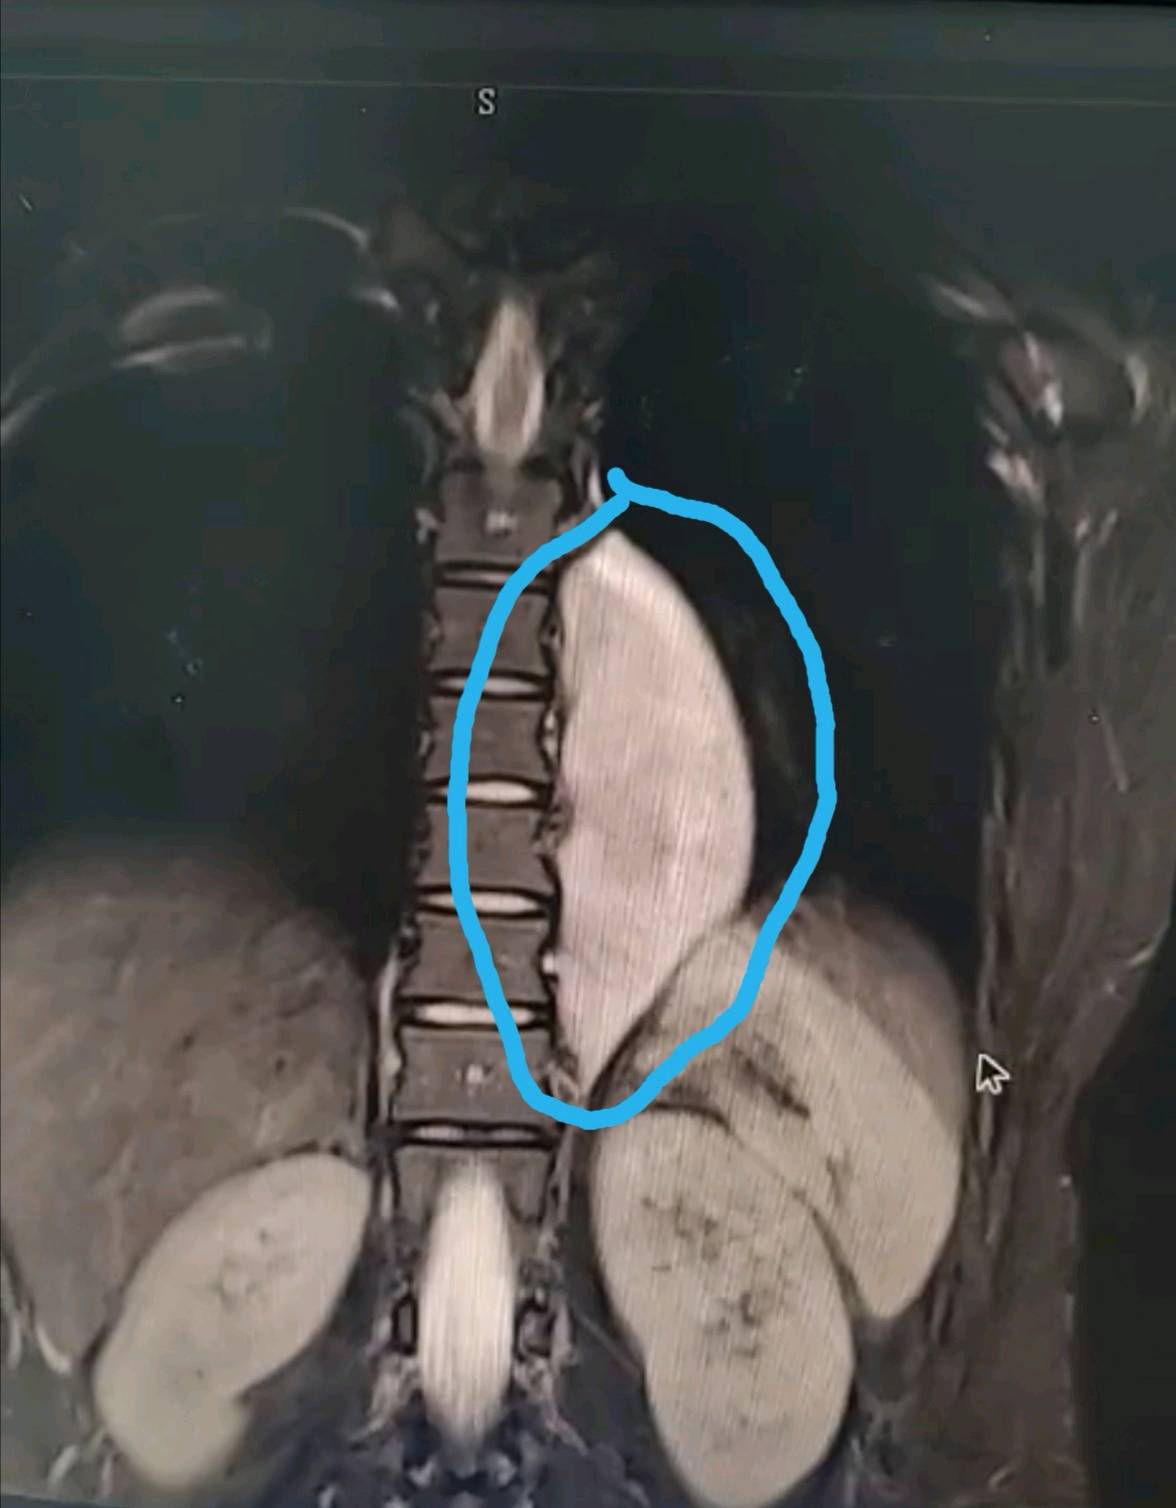

喔哦!这是什么?见下图:后纵隔脊柱旁巨大占位,横跨6个椎体,长达12cm。患者女性,22岁,单位体检CT发现(大部分由于心脏,纵隔器官的遮挡需胸部CT检查才能发现),运用我们的微创单孔3cm切口胸腔镜技术完美切除,术后4天顺利出院。术后诊断为罕见的胸交感节神经细胞瘤,此瘤的特点虽大部分是良性,但喜欢往缝隙里长,比如椎间孔,有报道以截瘫或神经症状而就诊的,本例肿瘤边有主动脉大血管,底有肋间神经血管,椎间孔,脊髓,任何一处都损伤不得。

3cm切口切除12cm的大肿瘤。胸腔镜微创外科的魅力。